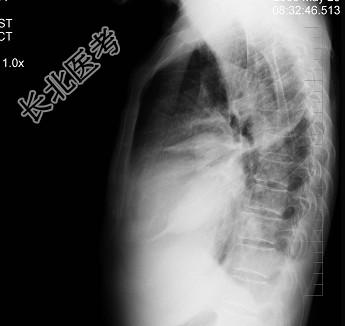

- 单项选择题患者女性,70岁, 胸闷、气逼数年,无明显发热、胸痛, 如图最可能的诊断是 ( )

A、心包积液并右水平裂积液

B、心包积液并右下肺炎

C、心包积液并右斜裂积液

D、心包积液并右双叶间裂积液

E、气胸